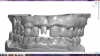

The next case follows the digital protocol for fully guided surgery and prosthetics. A CBCT radiograph, digital impression, and digital photography were the cornerstones to the success of this case. The 3D data set was electronically delivered to the dental laboratory. The data were merged and the process to develop the plan was initiated. The use of CBCT was essential in this case, particularly due to minimal space for placement of individual implants and single-unit crowns. The patient's chief concern was that she wanted to have single-unit crowns instead of fixed crown-and-bridge restorations because she was worried that she would someday find herself in an assisted-living facility; if that were to happen, she wondered, who would help floss under her bridge work? Her decision was to have single implants with individual crowns. CBCT technology is much more accurate in evaluating space maintenance and management.10 Periapicals in the past were rather close for calculating spacing; however, the CBCT identifies the buccal-lingual dimensions as well as the mesial-distal measurements. On review of the completed proposals for implant placement and provisionals, it was determined that there was sufficient spacing for implant placement to allow appropriate emergence profiles for the provisionals and then eventually the final single-unit cemented crowns. The proposal was accepted, and a 3D-printed surgical stent was fabricated, along with the PMMA provisionals (Figure 29 through Figure 35).

Fig 29. Preoperative Panorex.

Figure 29

Fig 30. Preoperative periapical radiograph.

Figure 30

Fig 31. Digital diagnostic wax-up.

Figure 31

Fig 32. Digital provisional proposals.

Figure 32

Fig 33. CBCT imaging merged with scanned impressions.

Figure 33

Fig 34. Implant placement proposal.

Figure 34

Fig 35. Digital proposal of the surgical guide.

Figure 35